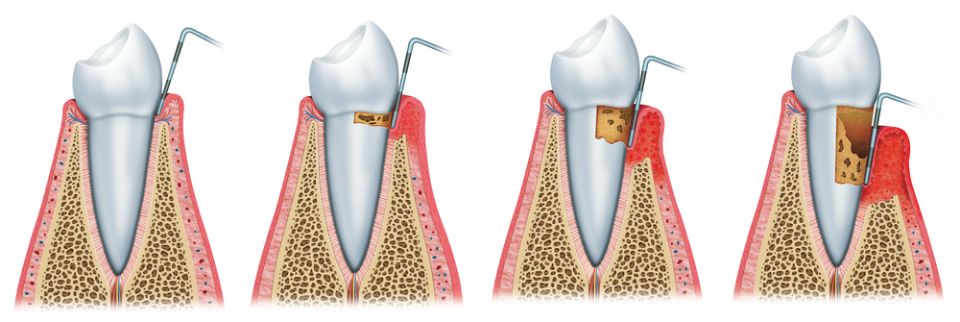

Periodontics and periodontal surgery

Periodontics is the dental specialty dedicated to the study of the periodontium or the supporting structure of the teeth. It encompasses the prevention, diagnosis and treatment of diseases that affect these tissues that surround and attach the tooth to the bone (gingiva, root cement, periodontal ligament and alveolar bone).

Among the best known periodontal diseases we find:

Gingivitis that causes inflammation and redness of the gums and possible bleeding when brushing.

Clinically periodontitis presents the signs of gingivitis but is also accompanied by the loss of the tissues that support the tooth: the periodontal ligament and the alveolar bone, causing the mobility of the tooth and future loss of it if it is not treated.

Our main objective is the prevention of the appearance of periodontitis and if it is diagnosed, treat it in order to eliminate the inflammation and be able to stop its progression. For this reason, it is important that the patient has a good habit of oral hygiene and attends the regular check-ups and visits of the dentist.

Sometimes we cannot treat periodontitis only with conservative treatment and we must resort to surgical techniques to achieve better results, for example with periodontal surgery.